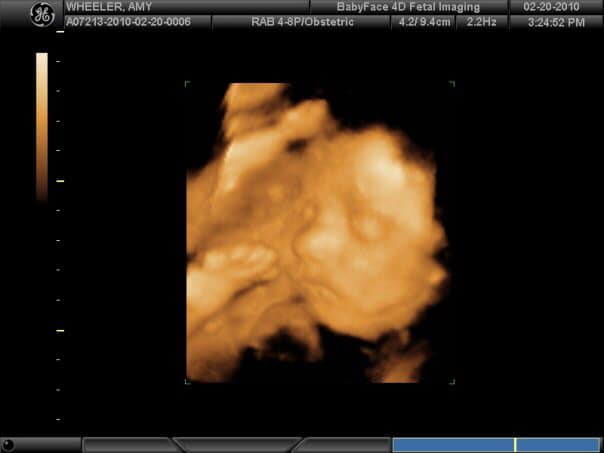

“I remember being so confident that we were having a healthy baby girl. (Even though we didn’t know the gender yet). When I saw her and the U/S tech said “its a girl” I just felt so complete and said “I know”. I just knew it. My first “mother’s intuition” was right and it made my heart so full.” -Amy

“After 2 girls I was certain we would have a third. As soon as I saw this, “is that what I think it is?!” As I lift my jaw off the floor.” -Lauren